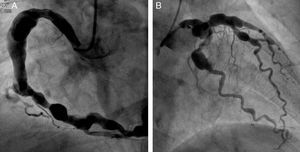

Right and left coronary angiography showing severe diffuse aneurysmal coronary artery disease. (A) Selective right coronary angiogram in left anterior oblique view showing a large aneurysm involving the proximal and mid segments of the right coronary artery (maximum diameter 12mm) as well as multiple smaller aneurysms in the distal segment of the vessel and in the posterolateral branch. (B) Selective left coronary angiogram in right anterior oblique view showing multiple aneurysms involving the distal portion of the left main coronary artery (LMCA), the proximal and mid segments of the left anterior descending (LAD) coronary artery and the proximal segment of the circumflex and the marginal branch.

A 67-year-old Caucasian man with a medical history of ulcerative colitis and hypertension presented with chest pain and diaphoresis ongoing for 12hours. His physical examination was unremarkable; electrocardiography revealed inverted T waves in leads I, aVL and V4–V6, and troponin I levels were initially positive at 14.7ng/dl, reaching a maximum of 40.8ng/dl. Echocardiography showed hypokinesia of the lateral wall of the left ventricle and an ejection fraction of 0.51. Subsequent cardiac catheterization revealed diffuse three-vessel aneurysmal coronary artery disease without flow-limiting stenoses (Figure 1) and the image of a recanalized thrombus in the aneurysmal first diagonal (the culprit lesion).